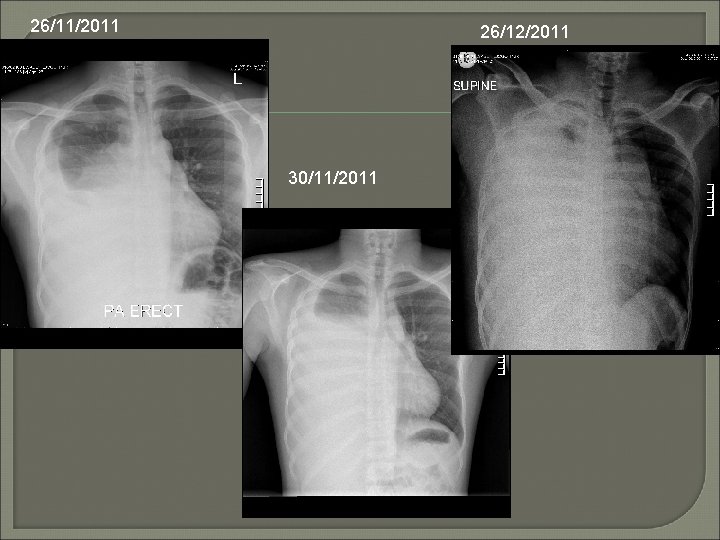

Back to our case. . . 26/12/2011

14/11/2011 (42 days earlier)

26/11/2011 26/12/2011 30/11/2011